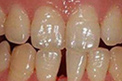

牙齿修复案例展示 TAIKANG BYBO DENTAL

泰康拜博美容修复根据每位患者的自身条件和需求进行选择,量身定制独有的个性化牙齿诊疗计划,让修复后的牙齿与整个脸型自然协调,和谐统一。并引进计算机断层扫描及时准确诊断口腔情况,科技与艺术结合,具有美牙少拔牙、时间短、牙齿坚固等优点。

该术以泰康拜博口腔的3-3-4-4黄金美齿法则漫步在国际齿科美容界,具有快速正畸,美齿、矫正、治齿一步到位的功效。并且,突破 传统美牙冠的弊端,将德国VITA比色术,美国微痛术和口腔内窥镜数码定位有机结合。